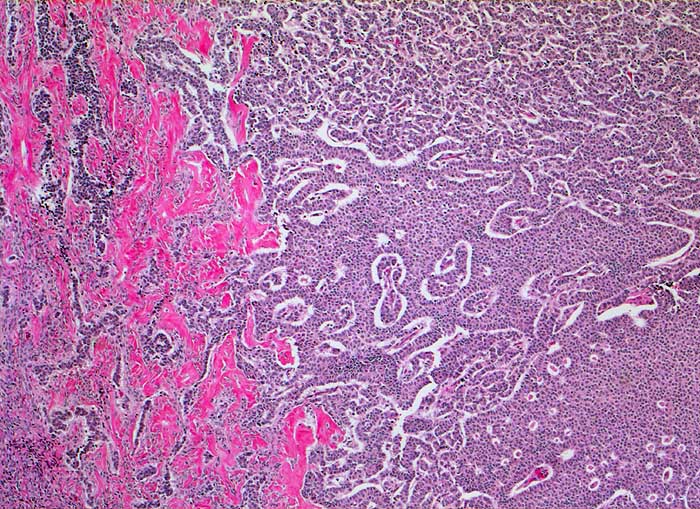

Granulosazelltumor des Ovars

maligner Tumor

Ovar

Morphologie